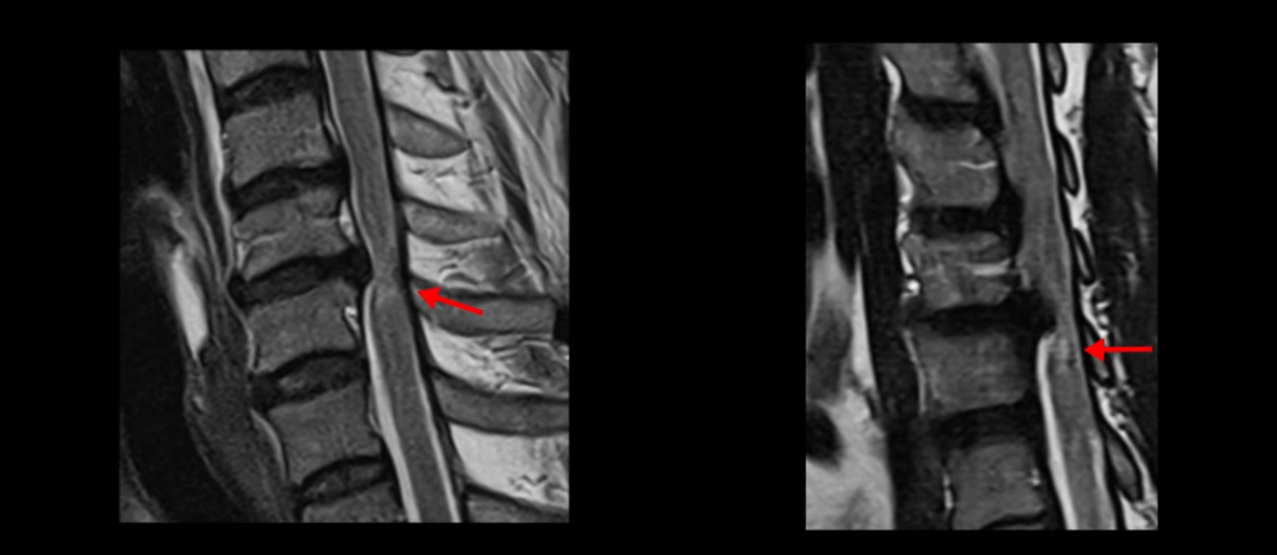

예전부터 허리통증이 있어서 허리에 문제가 있지 않나 싶어서 허리 MRI 촬영을 먼저 했어요. MRI 검사 했더니 척추관협착증이라고 하더라고요. 그래서 허리 수술이 필요하다고 해서 허리 수술하기 전에 손이랑 다리에 저림과 힘빠짐 증상을 얘기하니까 이게 척추 문제만이 아니고 다른 것도 문제가 있을 수 있으니까 MRI를 다른 쪽도 찍어보자고 해서 전체 다 찍은 거죠. 목이랑 허리 다 찍은 거죠. 검사 후 물어보니까 병원에 목을 치료하는 전문의가 있고 허리 쪽 전문의가 있는데 저는 허리 쪽 전문의랑 먼저 상담을 했거든요. 그러니까 그분은 일단 허리 쪽 먼저 하자고 해서 수술을 하게 됐어요. 척추관협착증이라고 허리 협착을 제거해야지 신경이 잘 흐를 수 있다고 수술해야 된다고 해서 허리 수술을 하게 됐죠.

척수 신경이 눌리고 손상되니까 양쪽 손과 양쪽 다리 모두에 증상이 생깁니다. 양손에 힘이 빠지고 젓가락질이 힘들고, 단추 끼우기도 어려워지고 다리에 힘이 빠지니까 걷기도 힘들어집니다. 양손과 다리의 감각도 떨어지고요. 그래서 이 환자분은 수술하더라도 목 수술을 해야 하는데, 엉뚱하게도 허리 수술을 받습니다. 처음에 병원에 갈 때 허리도 원래 많이 아팠다고 하니까 그 병원에서 목 검사와 허리를 함께 검사해 보고 허리 협착도 심하니까 허리 수술을 먼저 하자고 합니다. 그래서 허리 세 마디를 수술했습니다.

MRI 보면 무려 3마디의 허리 뒤쪽, 후궁 뼈 한쪽을 거의 다 뜯어내고

황색 인대를 대부분 다 걷어냈습니다.

문제는 이 허리 협착이 양손과 양쪽 다리 힘 빠짐의 원인이 아니었기에 수술 후에도 증상이 전혀 좋아지질 않습니다. 그나마 다행인 건 허리 여러 마디를 수술하면서도 나사를 안 박은 겁니다. 수술로 인해 허리 여러 마디에 손상이 생기니까 걷기가 더 어려워져서 결국 저희 병원에 오실 때는 휠체어를 타고 오셨습니다.